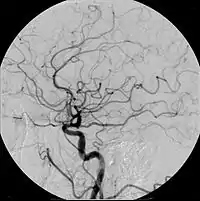

Современные контрастные препараты для внутривенного введения обычно содержат йод. Различают ионные и неионные контрастные препараты. Изначально были разработаны ионные йодсодержащие контрастные препараты, которые в настоящее время всё ещё используются в рентгенодиагностике. В неионных контрастных препаратах йод связан ковалентными связями, что заметно снижает риск осложнений. Имеет значение осмолярность контрастного препарата и концентрация в нём йода.